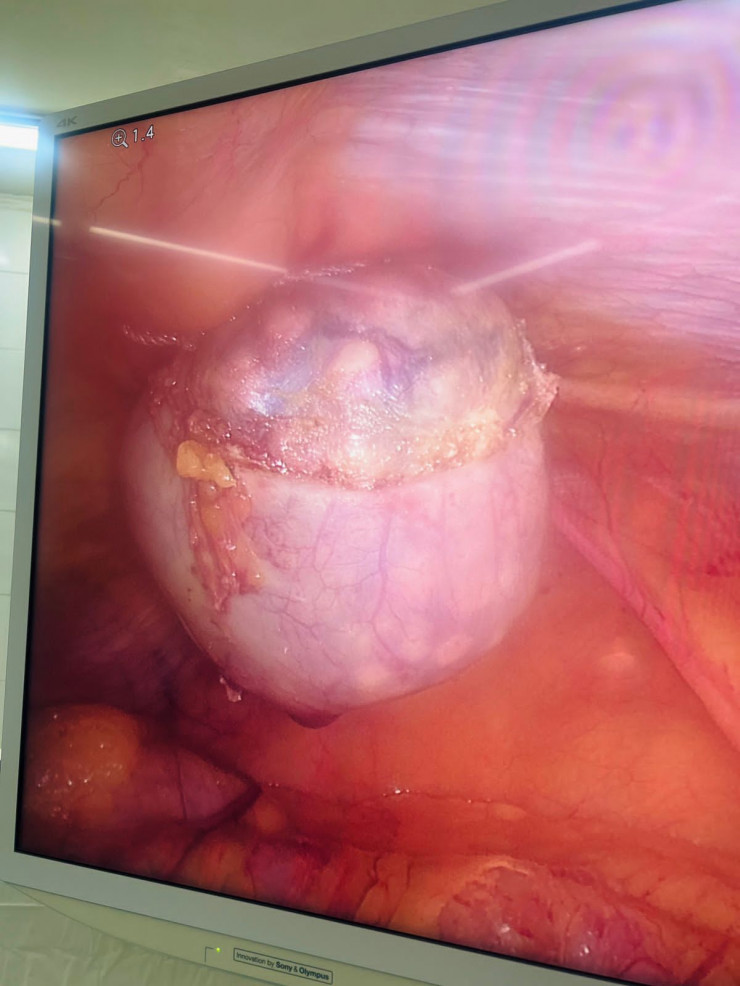

1730 камней извлекли хирурги из желчного пузыря алматинки Фото предоставлено пресс-службой ГКБ №7 Алматы

Более 1730 камней извлекли алматинские хирурги из желчного пузыря пациентки, передает корреспондент Tengrinews.kz.

62-летняя женщина поступила в городскую клиническую больницу №7 города Алматы в экстренном порядке с жалобами на боли в правом подреберье, тошноту, рвоту, сухость во рту. После обследования больной был выставлен диагноз: "Желчекаменная болезнь. Острый калькулезный холецистит". На следующий день ей была проведена лапароскопическая операция.

После удаления желчного пузыря из него было извлечено 1735 конкрементов диаметром от нескольких миллиметров до 1,5 сантиметра.

Специалисты отмечают, что желтый цвет камней обусловлен повышенным содержанием холестерина. Фото предоставлено пресс-службой ГКБ №7 города Алматы

"Эта операция обновила мой рекорд: в этот раз обнаружено более 1730 конкрементов (камней), и это только в желчном пузыре. В целях сохранения здоровья и предупреждения осложнений, связанных с ЖКБ, настоятельно рекомендую проходить профилактические и скрининговые осмотры", - отметил заведующий отделением хирургии №2 ГКБ №7 профессор Муса Сахипов.

Специалисты отмечают, что желтый цвет камней обусловлен повышенным содержанием холестерина.

Оперативное вмешательство прошло успешно, на 4-й день после операции больная выписана на дальнейшее амбулаторное наблюдение.